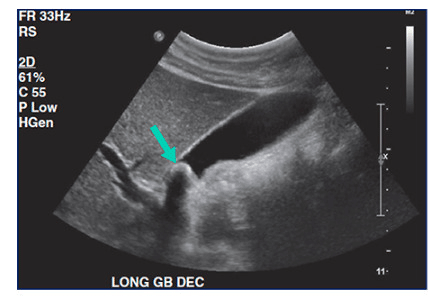

A vesícula biliar situa-se no leito hepático, entre os segmentos IVB e V, geralmente com forma piriforme. Seu comprimento habitual não ultrapassa 10 cm, e o diâmetro transverso deve permanecer abaixo de 4 cm. A espessura da parede normal não excede 3 mm, sendo fina e regular. O conteúdo deve ser completamente anecoico, sem ecos internos.

Na ultrassonografia, os cálculos aparecem como estruturas hiperecogênicas que produzem sombra acústica posterior. Frequentemente, movimentam-se com a mudança de decúbito, característica importante para o diagnóstico. O lodo biliar representa estágio inicial, identificado como material ecogênico no lúmen, geralmente sem sombra acústica.